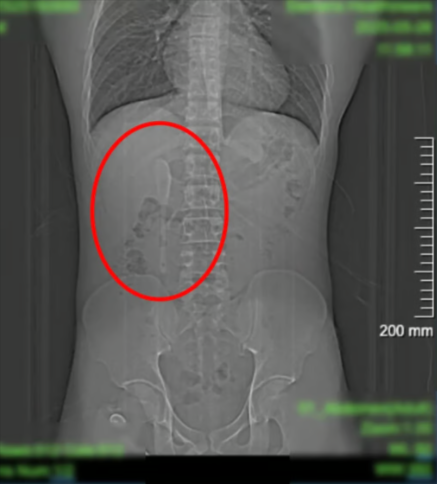

Когда 29-летнему китайцу провели томографию, то обнаружили там настоящую кофейную ложку длиной 15 см, которая застряла в его двенадцатиперстной кишке. Осмотр показал, что инородный предмет находился возле важной части желудочного тракта, а незначительное движение могло спровоцировать разрыв тканей, воспаление или даже внутреннее кровотечение.

Врачи на снимке увидели ту самую ложку

Врачи на снимке увидели ту самую ложку (фото: SCMN)